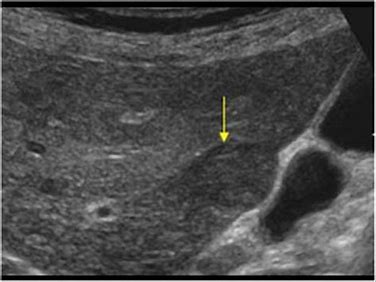

Abdominal Ultrasound

Ultrasound view

Ultrasound view...canine liver.